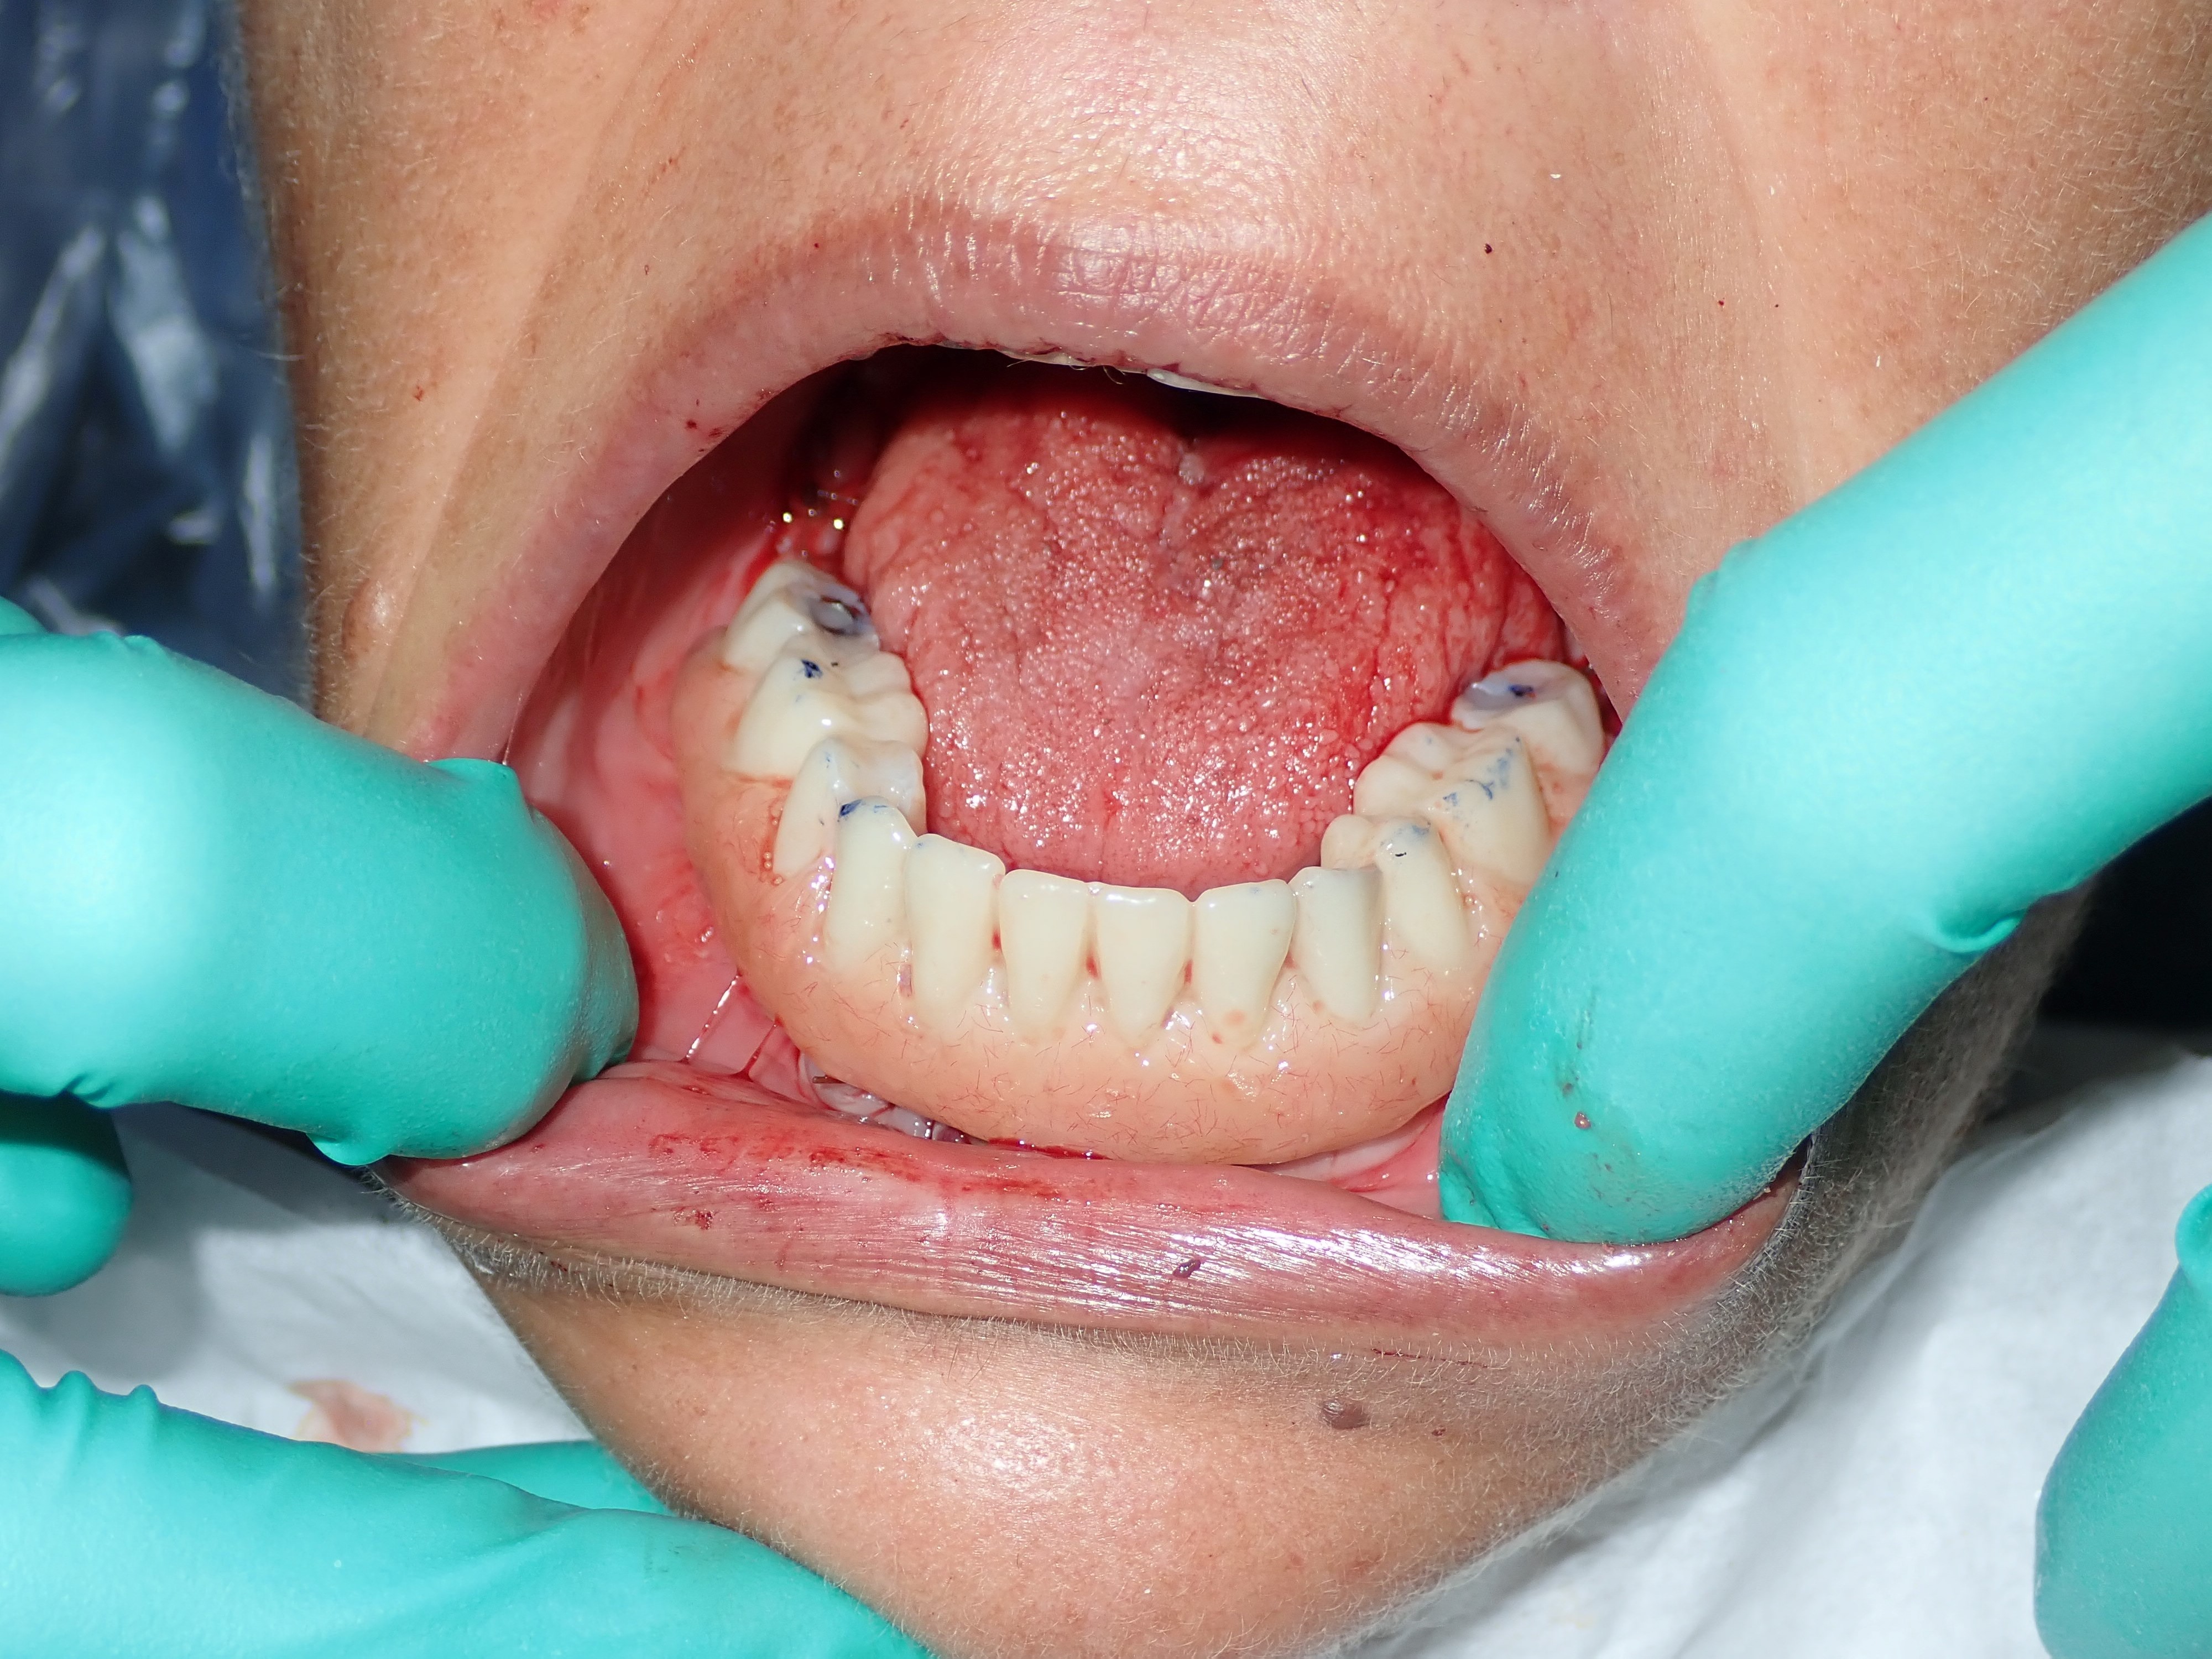

This mouth had recession on just one tooth with very little bone to support the tooth. The area needed support and thickness. The tissue was placed and the area now has thicker tissue to withstand the forces that the patient needs to place on it.